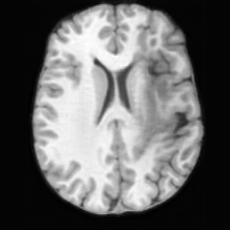

Unconditional Generation. Fig. 4 (a) presents examples of paired lesion masks and brain images generated by USB. Notably, although the paired lesion-brain generation begins unconditionally from random noise, USB produces lesion masks exhibiting diverse locations, sizes, and shapes, while simultaneously generating anatomically coherent brain images with embedded pathological patterns that spatially correspond to the generated lesions within each pair.

In Tab. 1, we present the first quantitative benchmark evaluation of both generation tasks. For the unconditional generation task, we generated 256 paired lesion–brain samples for each lesion type (stroke and WMH). For the conditional generation task, we used masks from the ATLAS and ISLES test sets as stroke lesions, and masks from the ADNI test set as WMH lesions. Notably, for each lesion type, the unconditional generation achieved superior quantitative performance, highlighting that the paired diffusion mechanism effectively generates coherent lesion-brain pairs through joint modeling between USBbrain and USBlesion. Additional generation results are provided in Suppl. A.